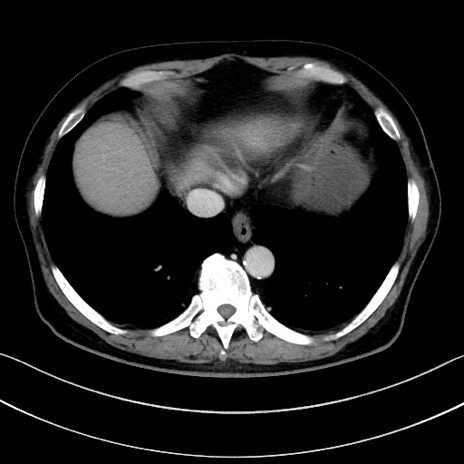

冠状断像

【症例】70歳代男性

【主訴】腹痛

【現病歴】今朝から腹痛あり。全体的に痛い。特に左上の方。排ガスが今日はない。冷や汗が出る。

【既往歴】直腸癌術後

【身体所見】左側腹部〜上腹部に圧痛あり。腹膜刺激症状明らかなではない。軽度反跳痛。左下腹部に術後瘢痕あり。

【データ】WBC 7700、CRP 0.02